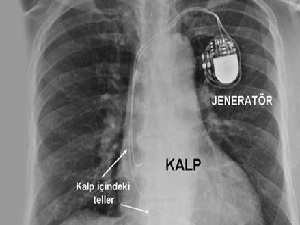

Kalp yetmezliği olanlara müjde!